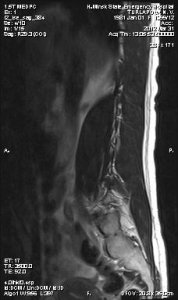

Снимки последнего МРТ прилагаю.

P.S. прикрепляю 10 фото с последнего МРТ, остальные фото не влезли... если нужно, буду пытаться прикрепить.

Снимки последнего МРТ прилагаю.

P.S. прикрепляю 10 фото с последнего МРТ, остальные фото не влезли... если нужно, буду пытаться прикрепить.